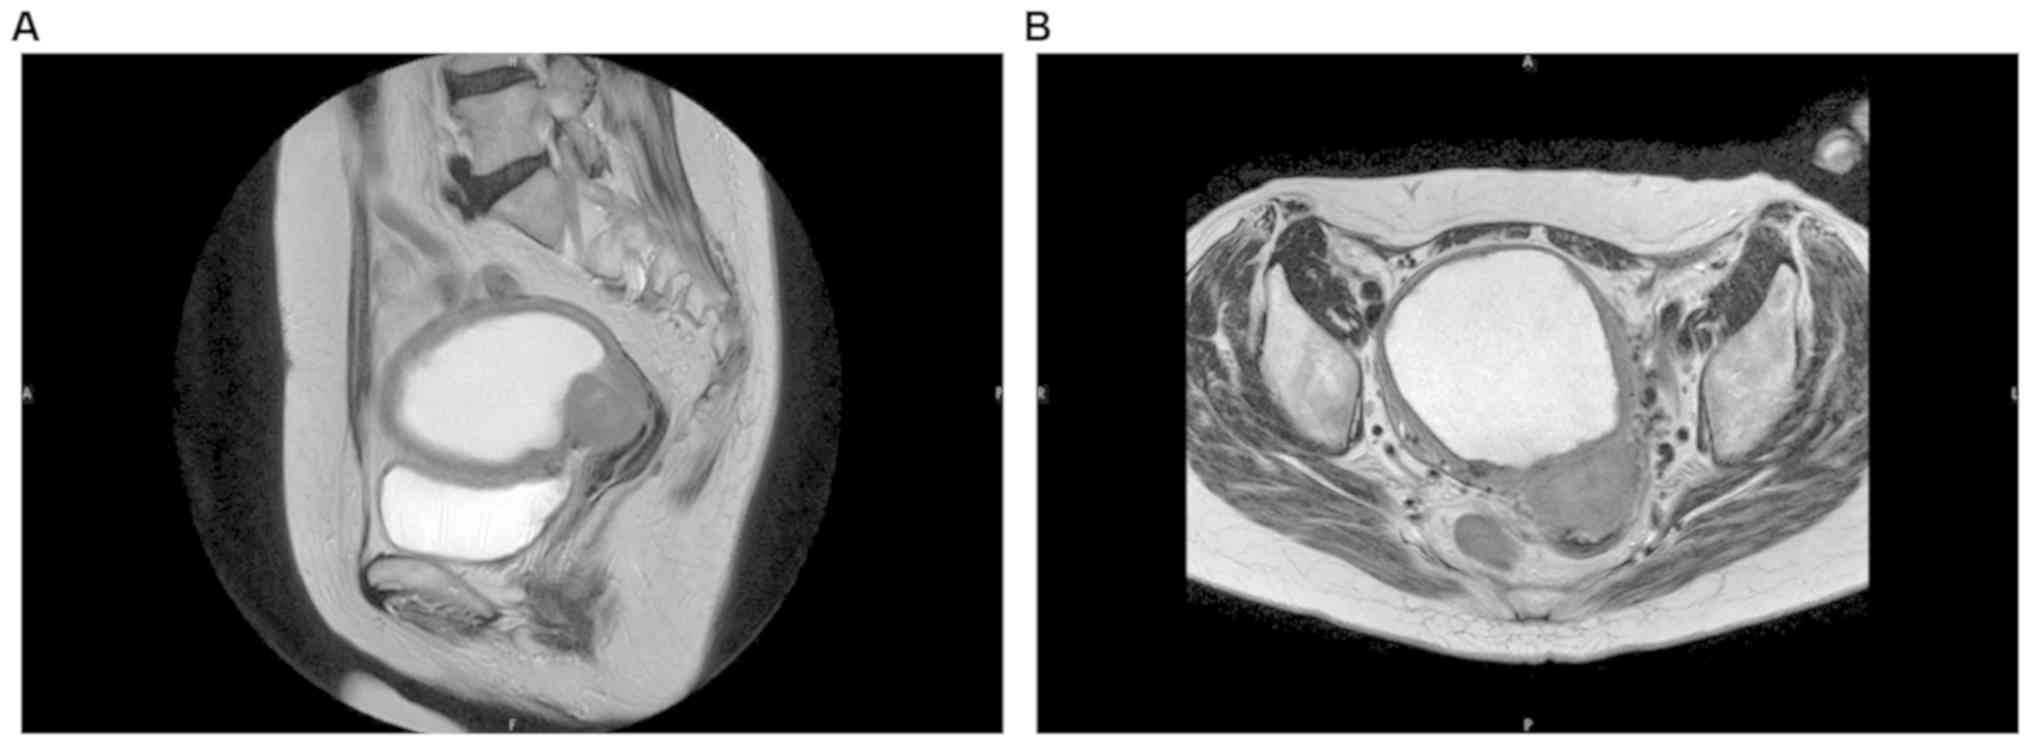

Squamous cell carcinoma of the endometrium is extremely rare, accounting for approximately 1% of uterine body malignancies. The present report describes a case of squamous cell carcinoma of the uterine body arising from ichthyosis due to persistent pyometra. A 68‑year‑old Japanese woman, gravida 1 para 1, was referred to the Gynecological Department of Tokyo Women's Medical University, due to watery brown vaginal discharge which had persisted for 10 days. Pelvic magnetic resonance (MRI) imaging revealed a tumorous lesion occupying the cervical uteri, measuring 3 cm in diameter, and pyometra. The endometrial biopsy specimen obtained after drainage of the purulent fluid in the uterus was insufficient for obtaining a definitive pathological diagnosis. Under a clinical diagnosis of cervical tumor and pyometra, total transabdominal hysterectomy with bilateral salpingo‑oophorectomy was performed. Histopathologically, two primary cancers were diagnosed, i.e., cervical endometrioid carcinoma and squamous cell carcinoma of the endometrium. The patient was treated with additional chemotherapy with carboplatin (area under the curve, 6) and paclitaxel (175 mg/m2). The patient has remained alive, without recurrence, for 1 year to date. In this case, preexisting cervical endometrioid carcinoma caused stenosis of the uterine orifice and also resulted in pyometra. The uterine body squamous cell carcinoma appeared to have been caused by persistent inflammatory stimuli to the endometrium. One must be cautious regarding cancer in elderly postmenopausal females presenting with pyometra. The findings in this case report suggest that chronic inflammation of the endometrium may be associated with primary squamous cell carcinoma of the endometrium.